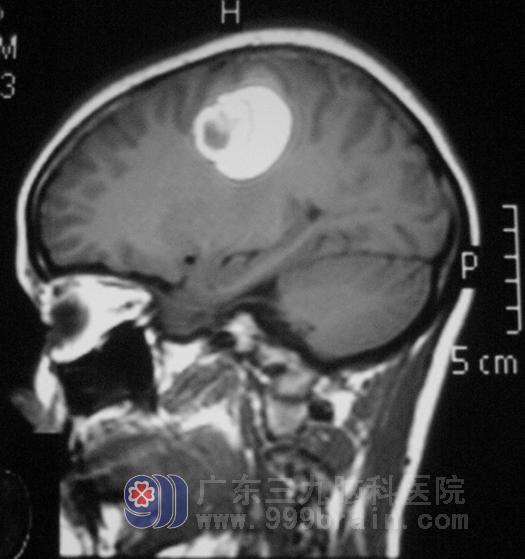

小燕10天前出现左侧肢体乏力,伴头痛、头晕,左手不能持物,行走困难。随即在当地医院行头颅CT检查,发现右侧额顶叶病变伴出血,进一步头颅MR检查,提示右侧额顶叶占位,直径约3cm,考虑星形细胞瘤可能。检查结果好似晴天霹雳,年轻轻的就被恶性肿瘤给盯上了,小燕和家人都难以接受这样的诊断。

为了继续求证,他们来到了广东三九脑科医院。入院体检:小燕左上肢肌力II级,左下肢肌力III级。综合神经外科的鲁明主任建议行头颅MRS检查(磁共振波谱),影像结果考虑非肿瘤性病变。结合小燕的病史及影像检查,鲁主任考虑血管畸形可能性大。

手术前